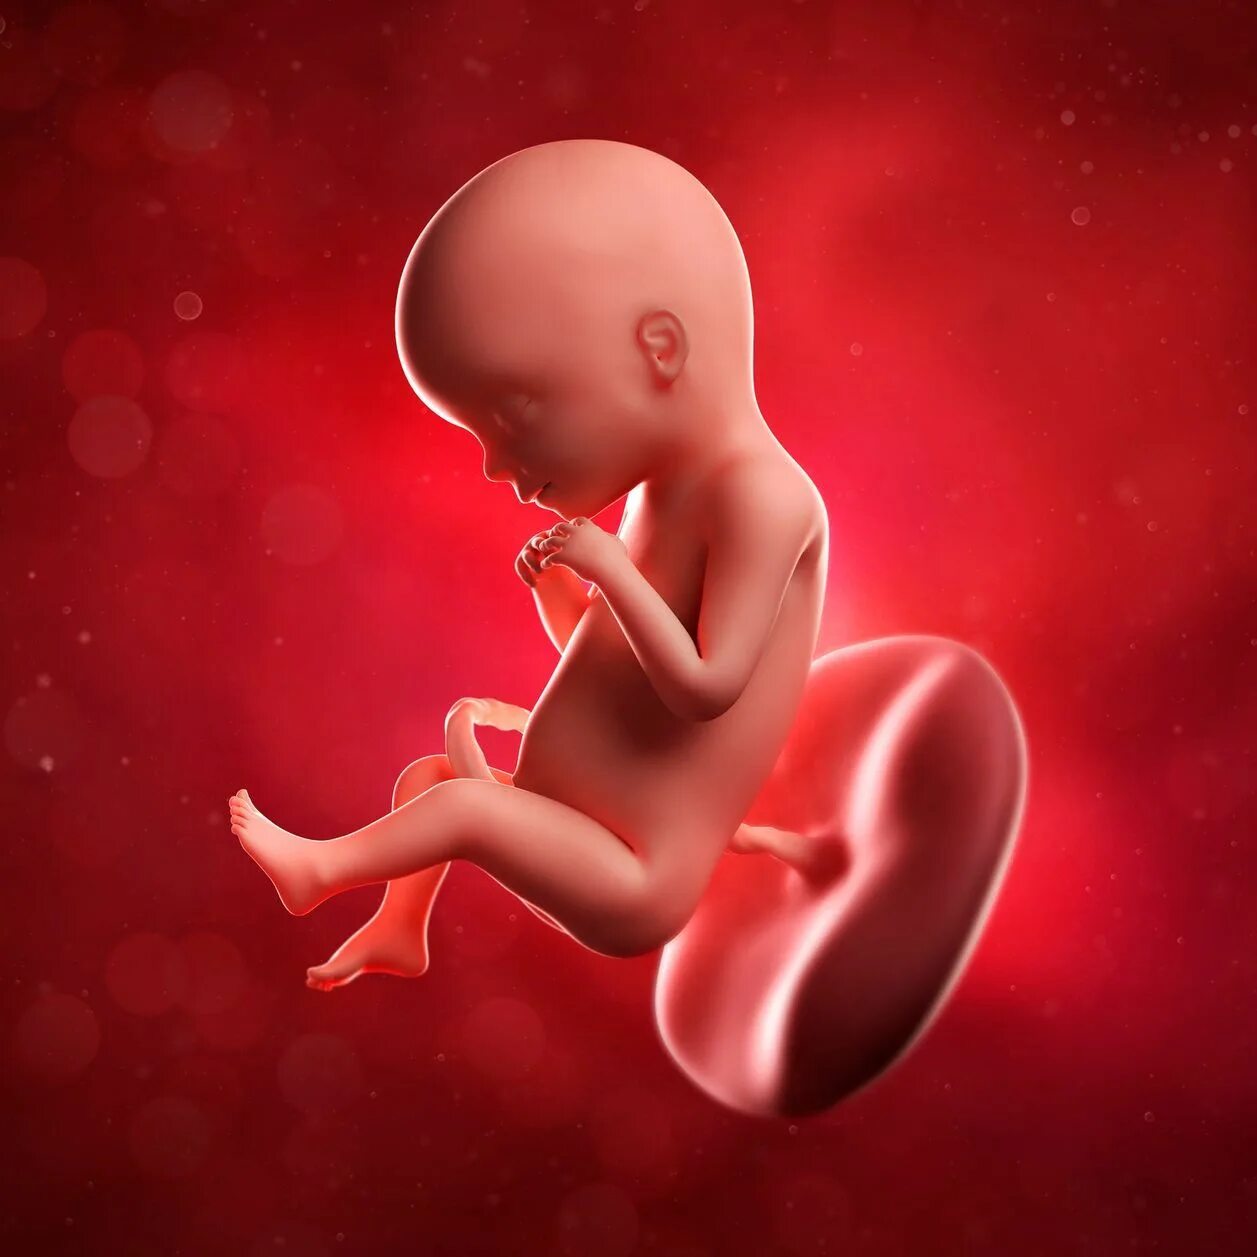

20 недель беременности ощущение